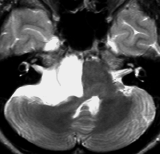

10代で発見された四丘体槽の類表皮のう胞です。左の画像,拡散強調像 DWIで真っ白に見えるので診断できます。真ん中は発見された時のもの,右側の画像は7年後です。ゆっくり増大してきたので,開頭手術(経テント法)で完全摘出しました。周囲の血管や神経に癒着するのでそれほど簡単な手術ではありません。